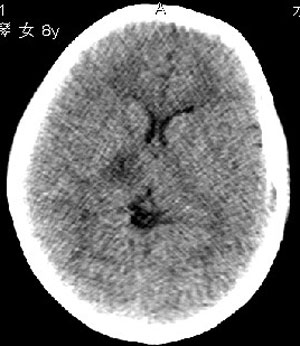

杨某,女,8y,家长述2006.10.13行破伤风疫苗注射后下肢疼痛,后自行粘贴膏药未见好转

,后续发现左上肢肢力下降。于2006.10.28在我院行ct检查,发现右侧基底节区片状低密度影,

无占位效应。ct值约:18~20hu。边界清晰,与相邻脑室无通连。未行增强扫描。余脑实质

未见异常。

右侧内囊后支、丘脑见片状低密度区,边界不清,无占位效应。

从ct图像看,准确地说病变是在右侧丘脑,累积右侧内囊后肢。